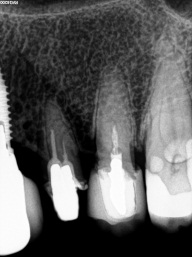

Em dentes de pessoas jovens, o canal é largo (amplo), com o decorrer do tempo e o envelhecimento natural, os canais vão diminuindo a sua luz ( o espaço interno ), tanto pela deposição continua de dentina, quanto por influências do meio externo, como trauma oclusal, caries, restaurações, e outros, com tudo isso, pode ocorrer desse espaço interno do dente ficar muito estreito (atresiado) ou até sumir por completo, ou seja completamente calcificado, quando chega nessa situação, é necessário o trabalho do endodontista para a localização dos canais calcificados e ou atresiados, limpeza e obturação com material indicado em cada caso.

Nos dias de hoje, existem técnicas e equipamentos que ajudam o profissional a conseguir o melhor resultados nessas situações, e uma delas é o uso do microscópio, que ajuda na localização das entradas dos canais atresiados e calcificados com maior precisão e segurança para o paciente.